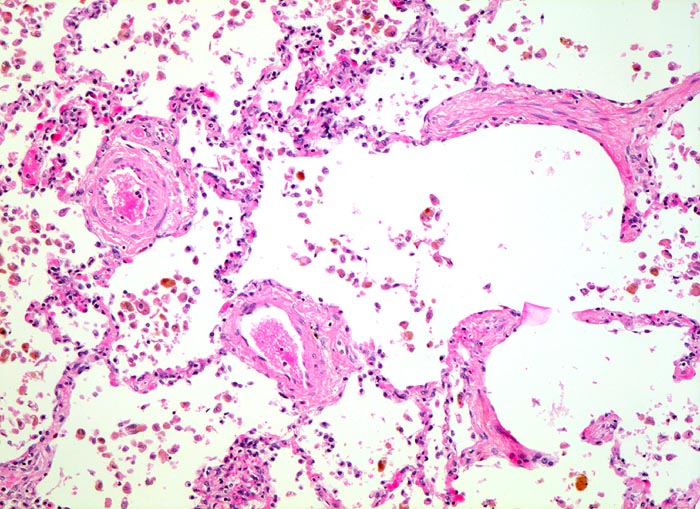

Herzfehlerzellen

vaskulär / Durchblutungsstörung

Lunge, Mediastinum mit Thymus

Sputum

Siderophagen lassen sich im Sputum nach intraalveolären Blutungen nachweisen. Intraalveoläre Blutungen infolge Linksherzinsuffizienz sind die häufigste Ursache. Andere Ursachen für intraalveoläre Blutungen sind Lungeninfarkte, eine toxische Kapillarschädigung, eine Vaskulitis oder Blutaspiration. Der Nachweis von Erythrozyten im Zytoplasma von Makrophagen spricht für eine frische Blutung. Hämosiderin wird nach 3-5 Tagen mit der Eisenfärbung nachweisbar. Als sicherer Hinweis auf eine ältere Blutung gelten >20% Siderophagen in der BAL.